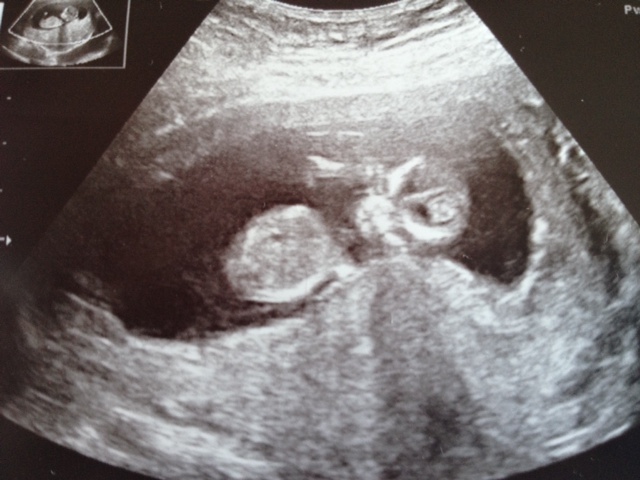

17+5 potty shot